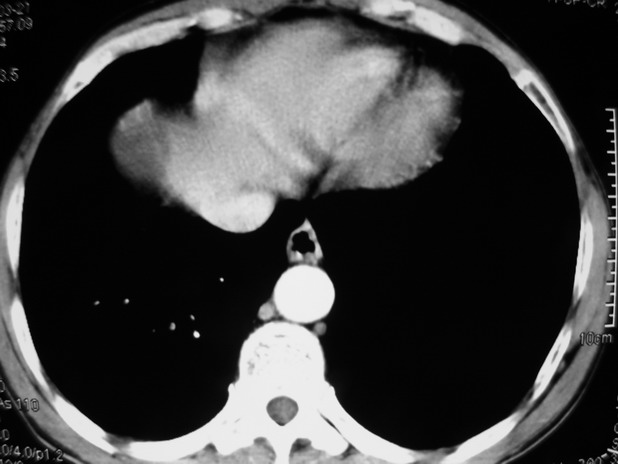

以下是引用余辉在2009-3-21 21:36:00的发言:[br]图像太乱了,建议楼主直接将强化数据按顺序列出来,病灶位置较表浅薄,有肝炎病史,灶内实性成分有显著强化,动脉期约60hu,考虑肝癌可能性大,进一步检查。